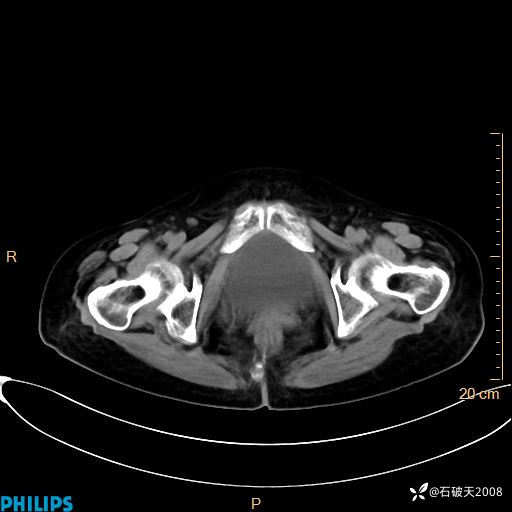

平扫

动脉期

MIP

静脉期